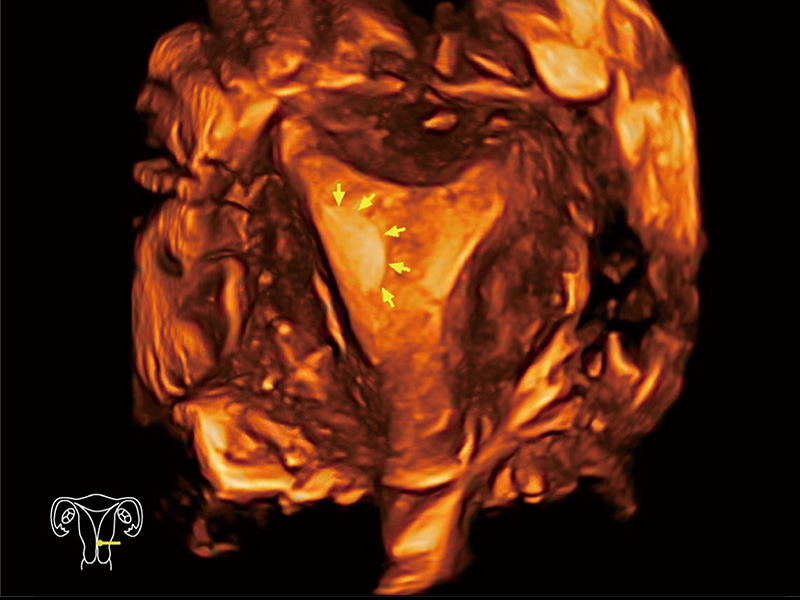

腔内容积探头

腔内三维成像技术获得显著提升,超大扇角在满足日常基础扫查的同时,支持卵泡自动测量及多种三维渲染模式,为您提供更多的诊断信息,尤其是在子宫畸形的诊断,内膜及肿瘤占位观测中起到了重要的作用。

中央型宫腔粘连